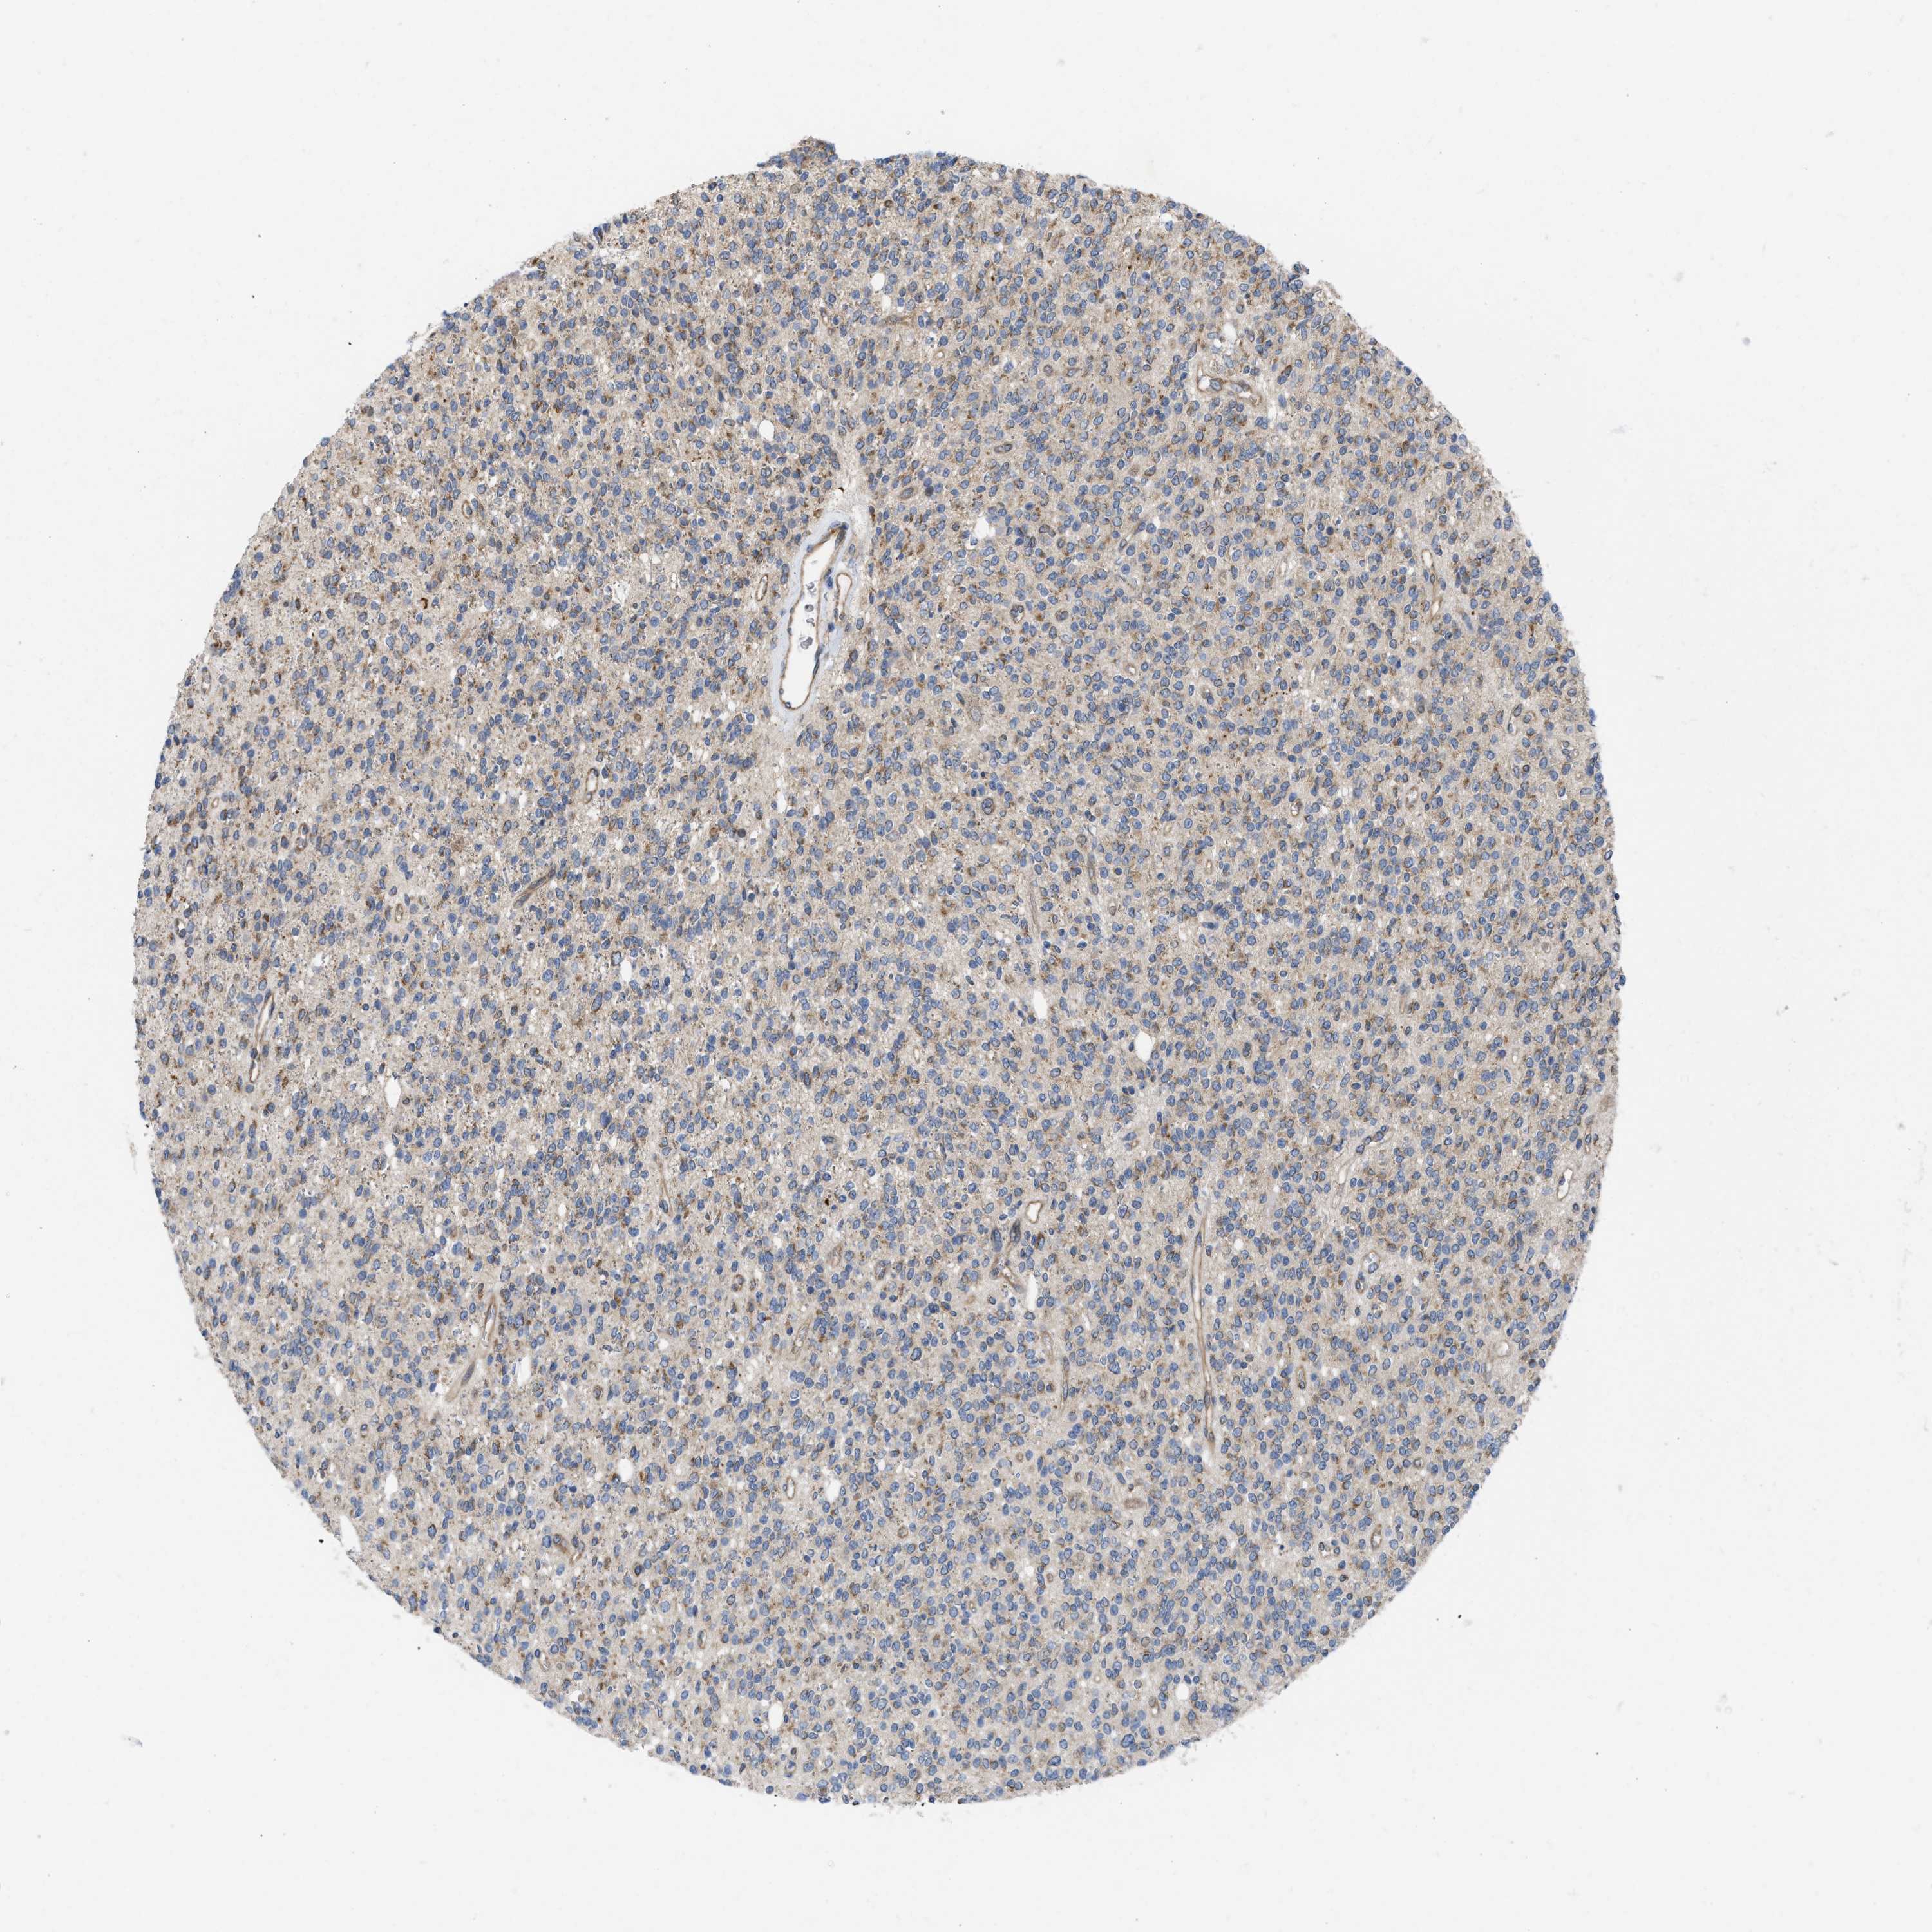

GLIOMA - Protein expressioni

A mouse-over function shows sample information and annotation data. Click on an image to view it in a full screen mode. Samples can be filtered based on level of antibody staining by selecting one or several of the following categories: high, medium, low and not detected. The assay and annotation is described here.

Note that samples used for immunohistochemistry by the Human Protein Atlas do not correspond to samples in the TCGA dataset.

Antibody stainingi

Antibody staining in the annotated cell types in the current human tissue is reported as not detected, low, medium, or high, based on conventional immunohistochemistry profiling in selected tissues. This score is based on the combination of the staining intensity and fraction of stained cells.

Each image is clickable and will lead to virtual microscopy that enables deeper exploration of all samples and also displays staining intensity scores, fraction scores and subcellular localization as well as patient and tissue information for each sample.

Antibody HPA019460

Staining

High

Medium

Low

Not detected

Intensity

Strong

Moderate

Weak

Negative

Quantity

>75%

75%-25%

<25%

None

Location

Nuclear

Cytoplasmic/membranous

Cytoplasmic/membranous,nuclear

Glioma, malignant, High grade

Glioma, malignant, Low grade